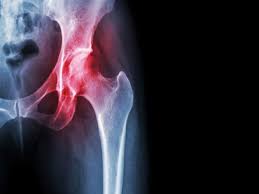

قصور الدورة الدموية لرأس عظمة الفخذ "النخر اللاوعائي"، الأسباب والأعراض والعلاج

يوضح الدكتور باسم عبد الغني درويش، استشاري جراحة العظام بمستشفى الهلال، عضو جمعية تنظير المفاصل بأمريكا الشمالية، عضو الأكاديمية الأمريكية للطب التجديدي، وعضو الجمعية السويسرية لتثبيت الكسور، أن قصور الدورة الدموية لرأس عظمة الفخذ هي حالة تؤدي إلى ضمور رأس عظمة الفخذ؛ نتيجة عدم وصول الدم إليها، وبالتالي تموت رأس العظمة ويحدث لها تسطح بحيث تفقد استدارتها.

ومع المشي والحركة يحدث تآكل في غضاريف المفصل؛ مما يؤدي إلى حدوث خشونة، وبالتالي الشعور بآلام حادة عند تحريك مفصل الفخذ.. وقد يظهر هذا المرض بعد فترة في مفصل الفخذ الآخر.

ويكشف الدكتور باسم درويش، استشاري جراحة العظام، أن المرض يبدأ بنقص تروية عظم الفخذ، وتوقف وصول الدم لجزء من رأس عظمة الفخذ لأحد الأسباب التى تم ذكرها؛ مما يؤدي إلى موت خلايا العظام الحية التى كانت تعيش فى هذا الجزء.. وهذه الخلايا هى المسؤولة عن الحفاظ على النسيج العظمي وترميم وإصلاح أي كسور دقيقة أو تلف يحدث فى النسيج العظمي أثناء الحياة اليومية والتحميل المتكرر على رأس عظمة الفخذ نتيجة الحركة والمشي والرياضة. وبالتالي ينتج عن موت هذه الخلايا أن التلفيات والكسور الدقيقة التى تحدث بصورة يومية لا يتم إصلاحها وتتفاقم التلفيات والكسور بمرور الوقت وتكرار التحميل على المفصل، إلى أن ينهار النسيج العظمي، ويبدأ حدوث فقدان استدارة رأس عظمة الفخذ.. وهذا يؤدي بمرور الوقت لحدوث خشونة بمفصل الفخذ.. إذا لم يتم علاج المرض مبكرًا.

المرحلة الثالثة: يكون هناك تسطح لرأس عظمة الفخذ فى الاشعة السينية ولكن دون حدوث خشونة (تآكل للغضاريف) بمفصل الفخذ.

المرحلة الرابعة: تكون هناك خشونة بمفصل الفخذ. نتيجة تآكل الغضاريف المبطنة للمفصل.